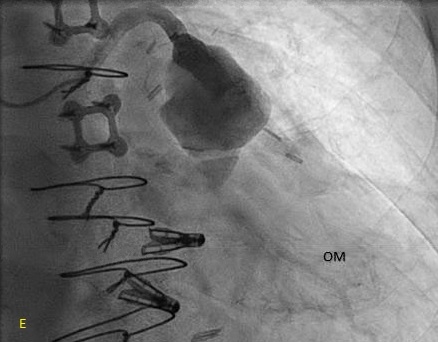

An 80-year-old patient with a history of coronary artery disease status post CABG in 2021, paroxysmal atrial fibrillation, heart failure with preserved ejection fraction, severe mitral regurgitation status post TEER-MitraClip, and moderate-to-severe aortic stenosis (aortic valve area 0.6 cm2, mean gradient 31 mmHg) presented with progressive exertional dyspnea, weakness, and lightheadedness. Transthoracic echocardiography confirmed moderate-to-severe aortic stenosis, and a cardiac CT was obtained for transcatheter aortic valve replacement (TAVR) evaluation. Imaging incidentally revealed a 3.1 cm SVG aneurysm with suspected intraluminal thrombus, prompting initiation of anticoagulation and left heart catheterization to further characterize the aneurysm.